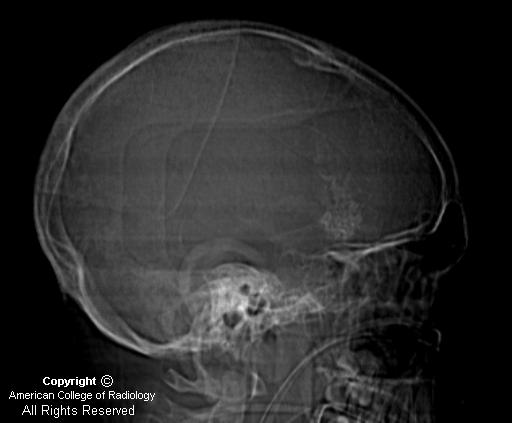

Home » Tram Track Sturge Weber Syndrome Radiology » Tram Track Sturge Weber Syndrome Radiology

Tram Track Sturge Weber Syndrome Radiology